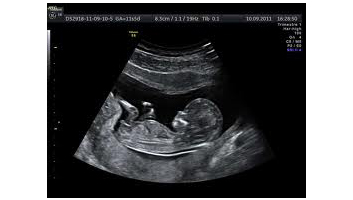

- Echographie doppler de la femme enceinte en 4D